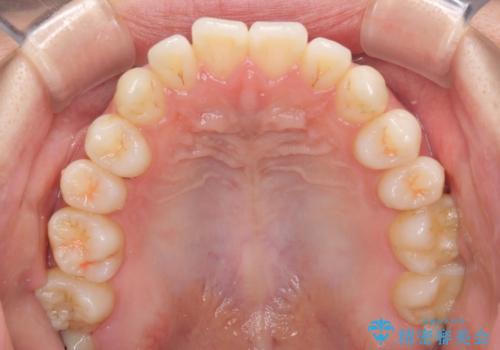

インビザラインで口を閉じやすく

- 下唇に上の前歯が当たることを気にして来院された患者様です。

上顎の親知らずを抜去し、歯列全体を後方に移動させるとともに、IPR(歯と歯の間を削る)を行うことで口元の閉じにくさを改善していくこととしました。

咬合力が強く、マウスピースを介した咬み込みが顕著であったため、奥歯の咬みにくさやIPRのスペースが改善しにくく、治療期間が思った以上にかかってしまいました。